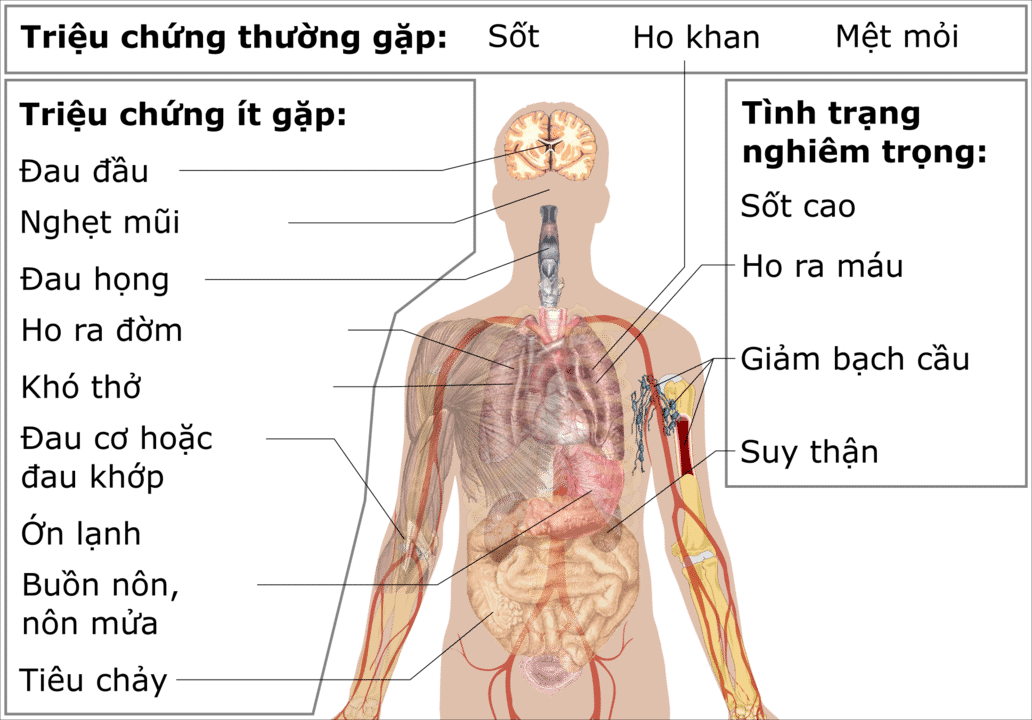

Các triệu chứng được báo cáo gồm sốt trong 90% trường hợp mắc bệnh, mệt mỏi và ho khan trong 80% trường hợp, 20% bị khó thở và suy hô hấp chiếm 15%. X-quang ngực đã tiết lộ các dấu hiệu ở cả hai phổi.

Dấu hiệu sống nhìn chung là ổn định vào thời điểm nhập viện của những bệnh nhân. Các xét nghiệm máu thường cho thấy số lượng bạch cầu thấp (giảm bạch cầu và giảm bạch cầu lympho).